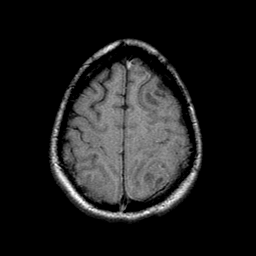

Sarcoma, MR Study #1 mr-t1 -- Slice #20

[Home][Help][Clinical] Slice 20